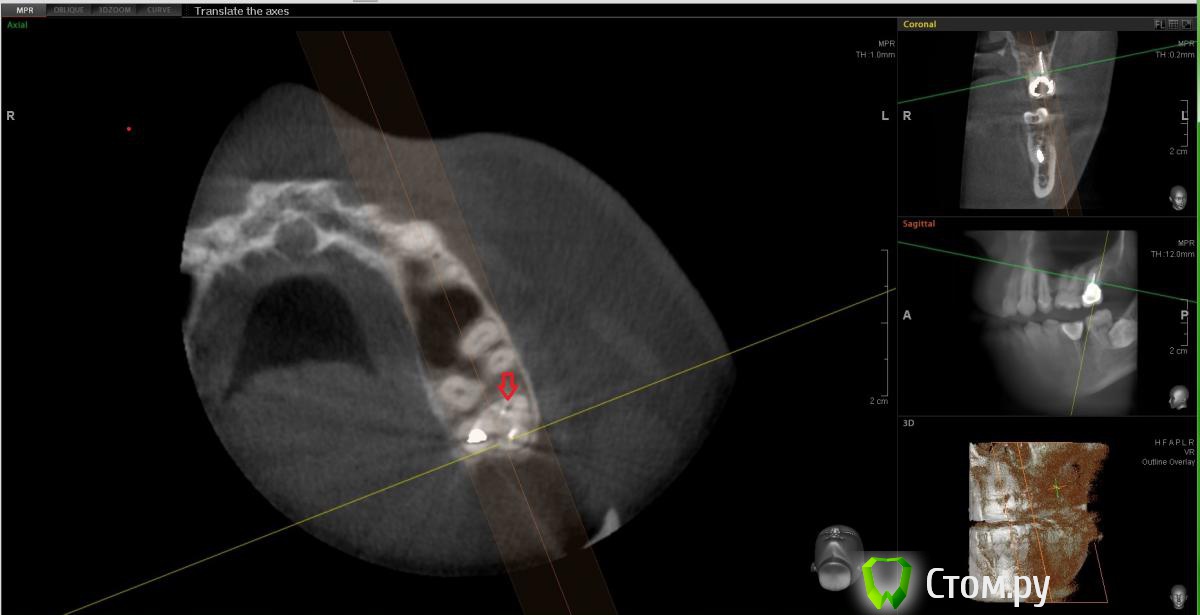

Еще один прицельный снимок этого зуба. Есть вариант того, что там пропущен канал?[/url]

Сначала предположила что есть пропущенный канал исходя из этого:

Но оказалось, что это как бы "пора"